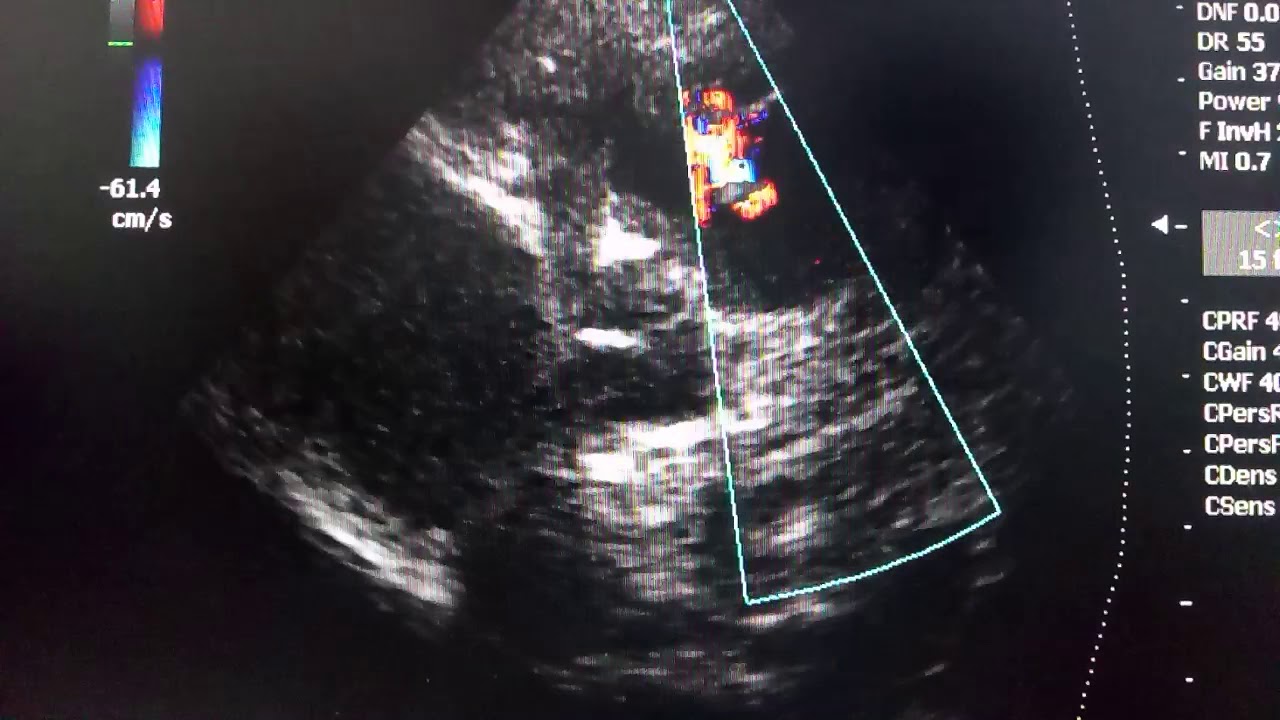

- Эхокардиография. Метод ультразвукового исследования, позволяет изучить внутреннее строение органа и выявить отклонения от нормы.